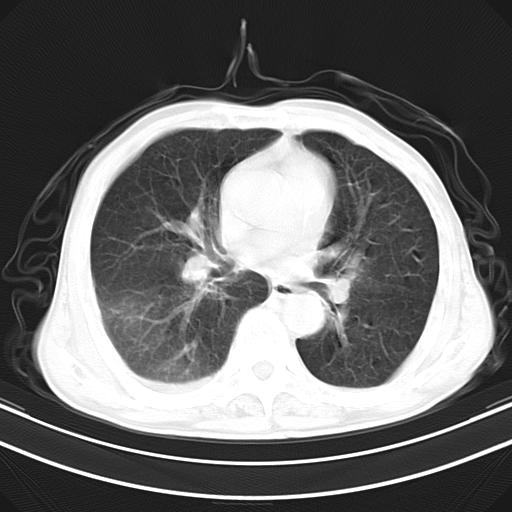

男,70,发烧咳嗽咳痰10余天,查痰结核菌阴性。否认以前有肺病史。治疗10天后症状减轻。 img]/upload/forum/2009/12/302117469692.jpg[/img]

影像所见:右上肺见一巨大厚壁空洞,内壁欠光整,右上肺广泛斑片状、大片状模糊阴影。

影像所见:右上肺见一巨大厚壁空洞,并见分隔,内壁欠光整,右上肺广泛斑片状、大片状磨玻璃阴影。